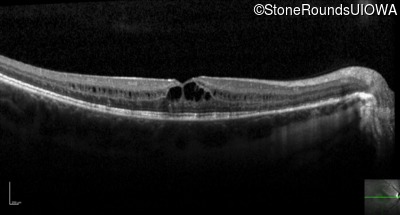

Optical Coherence Tomography - Left - 20/50

Exemplar / OCT Stack

OCT Stack